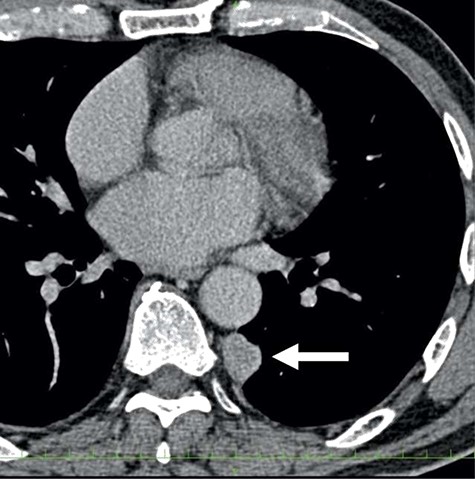

A 78-year-old man complained of chest pain for 2 months and was admitted to our hospital. Computed tomography (CT) scans revealed a tumor in the left thorax. He had undergone prior surgical resection of the primary SFT and recurrent tumor at 11 and 2 years before the current presentation. The CT findings of the primary tumor revealed a solitary, well-circumscribed and no signs of invasion (Fig. 1). Intraoperatively, the primary tumor arose from the visceral pleura and the resection was performed by wedge resection. The resected tumor was an oval, elastic soft mass with homogenous milky white cut surfaces. Postoperative histopathologic and immunohistochemical findings were consistent with SFT, and the mitosis and malignant features, including nuclear atypia, necrosis or higher cellularity, were hardly seen. In contrast to the primary tumor, as shown in Fig. 2, the CT findings revealed that the current tumor extended through the neural foramen. Furthermore, the tumor had an osteoclastic progression into the thoracic spine. Therefore, this tumor was considered to become malignant, and we considered the surgical complete resection is impossible. For histological confirmation, CT guided needle biopsy was performed. The histological findings of this recurrent tumor were identical to those of the primary tumor. The mitosis was hardly seen in this recurrent tumor. However, immunohistochemically, the MIB-1 proliferation index (Ki-67) of the primary tumor and the current tumor was 1.74 and 30.00%, respectively (Fig. 3A and B).

The computed tomographic findings of the current tumor; note the tumor extended through the neural foramen, and had an osteoclastic progression into the thoracic spine (arrow).